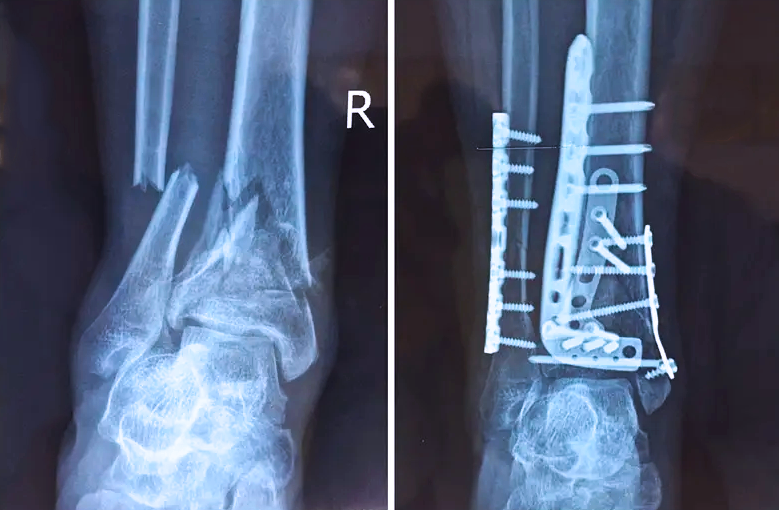

对于骨科医生而言,关节外的骨折是相对比较简单的,因为关节外的骨折允许我们复位的时候有一些偏差,但是如果骨折部位在关节内,我们就不能有任何的偏差。而且关节内的骨折是有关节面的,如果关节面不平整,就会导致患者以后出现创伤性关节炎等症状,或者出现长期的疼痛,甚至造成残疾。所以对于关节内的骨折,一定要做到“解剖复位”,就像搭积木一样,每个积木块、每个碎骨块都要完好的拼到一起,做到严丝合缝。

踝关节是人体中负重较大的关节,也是活动度较大的地方,所以对于足踝部位的关节内骨折,我们更需要做到“解剖复位”。对于这种关节内的骨折,尤其是踝关节内部的骨折,不仅需要进行X影像平片正侧位的拍摄,由于在二维影像上无法判断关节面的受损情况,往往还需要进行三维影像的检查。

在术前,我们需要做三维扫描的CT检查,我们必须要有CT的片子,还要有三维的重建。

在术中,我们怎么去判断关节面平不平整呢?常规的正侧位影像是不能判断的。有些医生为了准确的判断,可能会选择做开放性的手术,把关节暴露出来,在眼睛的直视下判断关节面平不平整。但是关节全部打开,无疑增加了病人的创伤,而且增加了患者的恢复时间。所以如果在术中我们有三维影像的支持,对医生做手术而言就会事半功倍,而且能够大大的增加手术准确度,增加患者术后的预后。所以在术中有三维影像的支持是非常必要的!